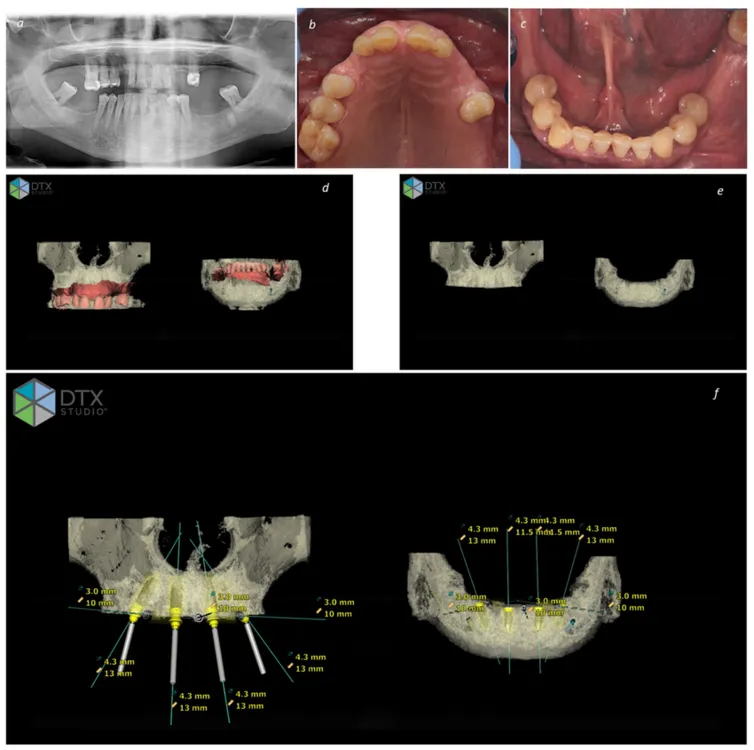

1. Comprehensive Evaluation

We begin with a detailed consultation, including 3D CBCT imaging, to assess your jawbone and customize your treatment plan.

On the day of surgery, implants are placed in strategic positions to maximize support—often using angled implants to avoid bone grafting.